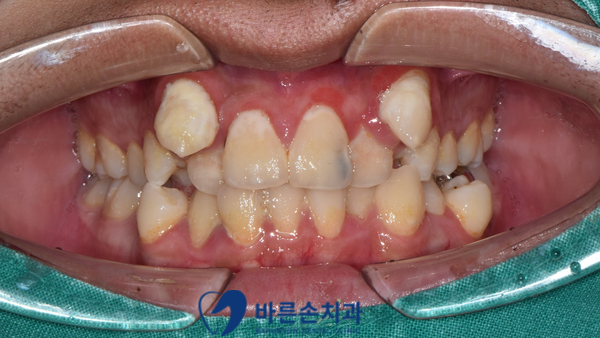

환자분 구강 사진입니다.

전반적으로 구강위생도 잘 되어있지 않았고, 앞니에 까맣게 충치가 생겨있네요.